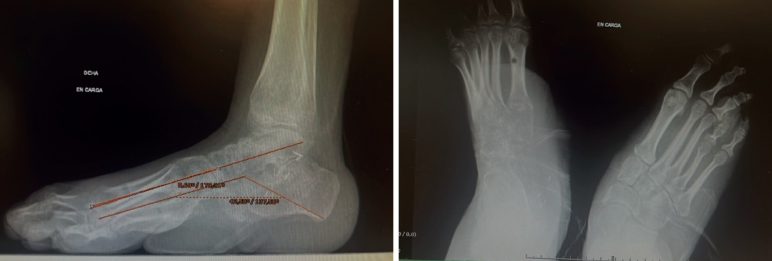

Además, se observa una normalización del ángulo de Meary y el de Costa-Bartani (Figura 5).

Figura 5. Radiografías en carga que muestran la normalización de los ángulos de Meary y Costa-Bartani.

El valor normal del ángulo de Meary sería menor de 10° y nos sirve para evaluar la alineación del arco longitudinal medial del pie y cuantificar deformidades sagitales(11).

El valor normal del Costa-Bartani es entre 120 y 130°, y evalúa la altura y la estabilidad del arco medial, y el equilibrio estructural del pie(12).